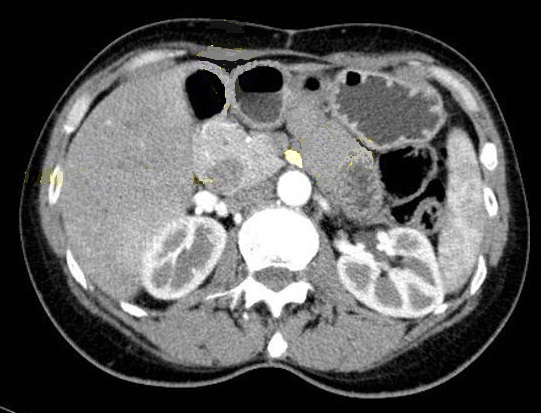

Aspect radiologique d'un

pancreas annulaire incomplete . La la tete

hyperdense , portion vevtral du pacreas se

forme un anneau in complete un tier autour le

duodenum . Le duodenum est en visible a

hypodense pres le pancreas ( fleche jaune ) . Image

radiologique TDM plus C+ ,coupe axiale , temps

arteriel |

Image radiologique TDM en

coupe axiale plus C+ d'un pancreas annulaire in

complete . La tete du pancreas est en forme une

rotation incomplete 1/3 autour le duodenum D2 (

fleche rouge ) |